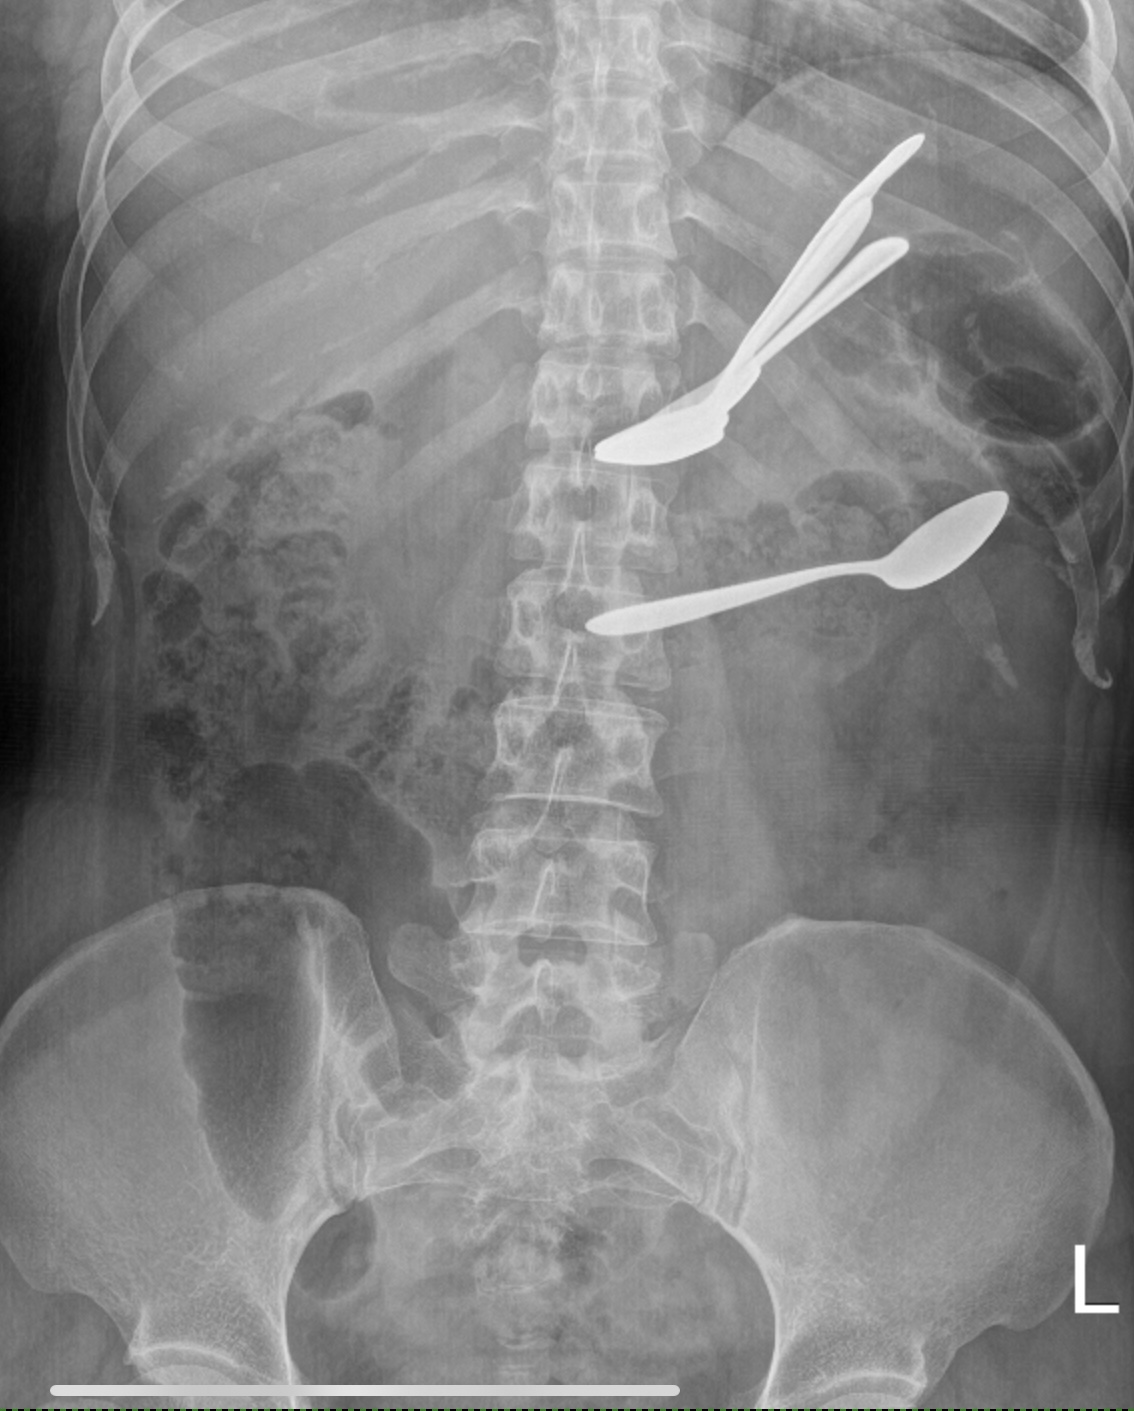

Foreign bodies in the stomach and transverse colon on abdominal X-ray